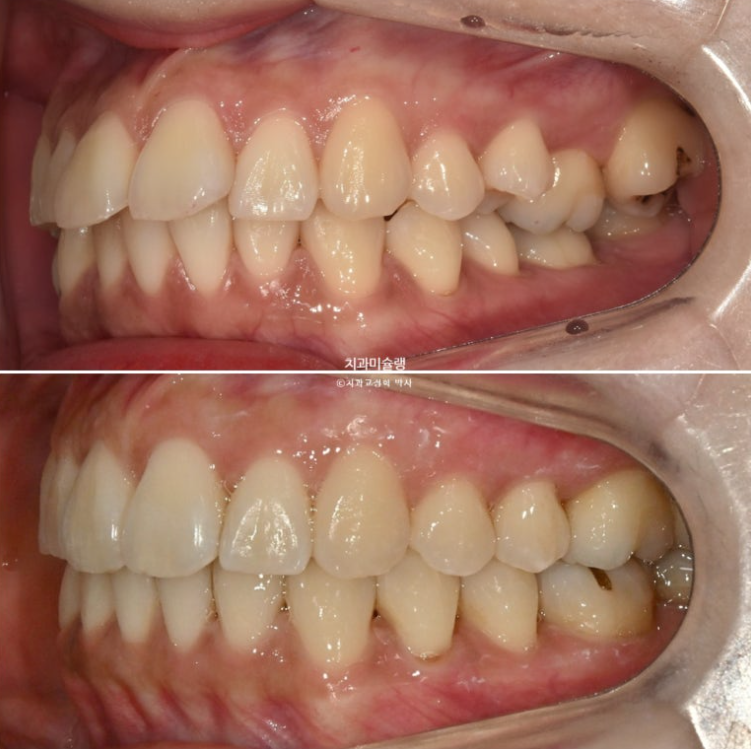

2년 전 교정치료를 위해 온 30대 환자분입니다. 파란 화살표 볼쪽으로 튀어나간 어금니들이 보입니다.

중심선 불일치도 보입니다.

가위교합으로 인한 저작 불편

앞니뻗침으로 인한 돌출이 있고

좌측에는 가위교합이 소구치에 하나 대구치에 하나 총 2군데 있습니다.

교합을 담당하는 어금니 중 절반이 가위교합 상태이니, 좌측으로 씹기가 힘든 상태입니다.

우측으로만 씹다보면 치아나 잇몸에 무리도 가고 주로 씹는 쪽 얼굴 근육이 발달하여 비대칭 처럼 보이게 됩니다.

아래 큰어금니는 안으로 쓰러져 있습니다.